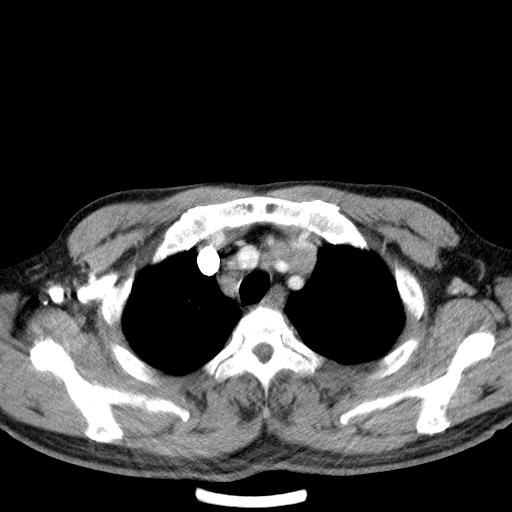

先行ct平扫,纵膈内多发软组织影,ct值约为36hu,以下为增强扫描和腹部平扫。

经典?纵膈多发肿大淋巴结。腹膜后未见异常。

淋巴瘤?胸腺瘤?

支持淋巴瘤

淋巴瘤可能

1)考虑淋巴瘤。2)双侧少量胸腔积液。